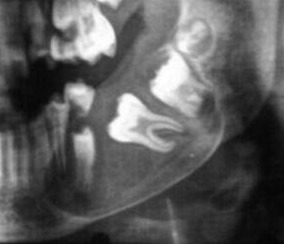

EXTRAORAL PICTURE RADIOGRAPHIC APPEARANCE HISTOPATHOLOGICAL PICTURE

RADIOGRAPHIC APPEARANCE HISTOPATHOLOGICAL PICTURE